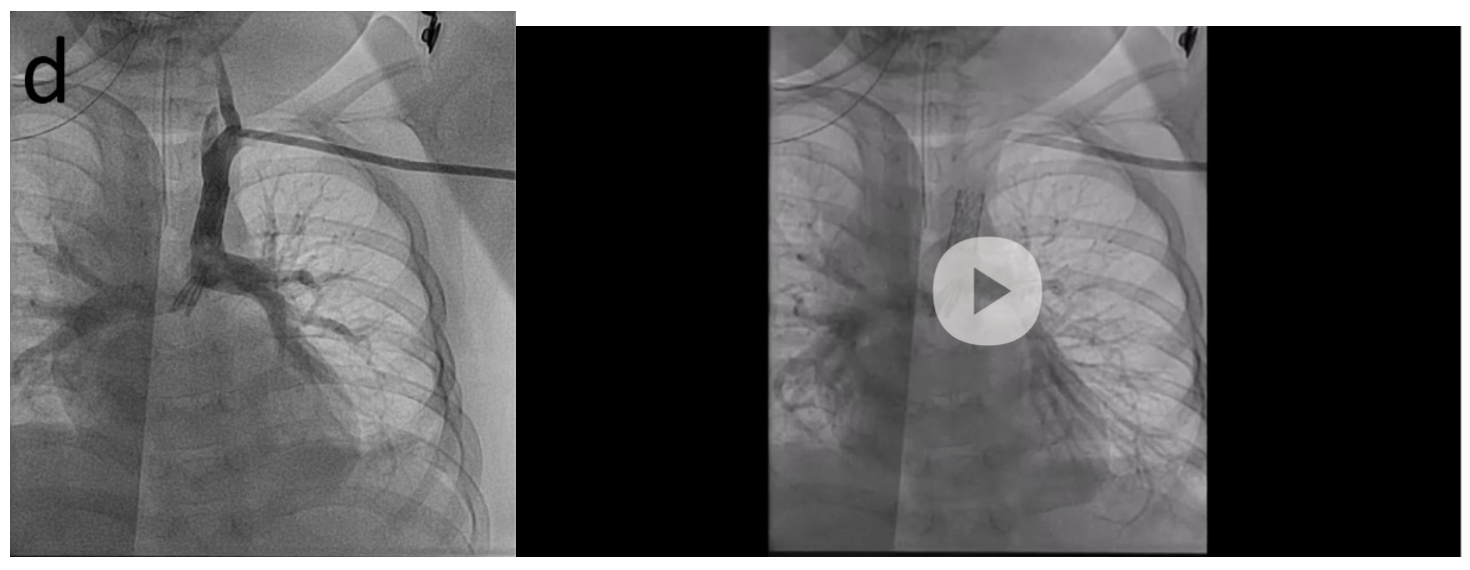

Aortic angiography showed a right aortic arch with only right carotid and right subclavian arteries and retrograde filling of the left carotid, left subclavian artery, and pulmonary arteries (Figure A/B, Video 1). Angiography of the left subclavian artery showed the tortuous, stenotic arterial connection between the pulmonary arteries and left subclavian artery (Figure C, Video 2). After stent placement, there was marked improvement in the caliber of the vessel and systemic saturations (Figure 1D, Video 3). Cerebral NIRS monitoring was used during the procedure with no change after stent placement. She has maintained reasonable saturations and has been seizure-free for over 3 years without neurologic deterioration or further cardiac intervention.